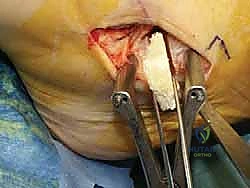

الخطوة الثالثة: الشق الجراحي والوصول الآمن

يتم عمل شق جراحي دقيق ومدروس على الجانب الداخلي للكاحل، خلف وتحت الكعب الإنسي. يستخدم الدكتور هطيف تقنيات تشريحية دقيقة لحماية الهياكل الحيوية المحيطة، وخاصة العصب الصافن (Saphenous Nerve) والوريد المرافق له، لتجنب أي تنميل أو ألم عصبي مزمن بعد الجراحة.

الخطوة الرابعة: تقييم وإصلاح رباط الدالية (Repair vs. Reconstruction)

بمجرد الوصول إلى رباط الدالية، يتم تقييم درجة التلف:

* الإصلاح المباشر (Direct Repair): إذا كانت أنسجة الرباط الممزقة ذات جودة جيدة (عادة في الإصابات الحديثة)، يقوم الدكتور هطيف بخياطتها مباشرة. يستخدم خطاطيف تثبيت عظمية (Suture Anchors) صغيرة جداً ومصنوعة من مواد متوافقة حيوياً (تذوب مع الوقت أو من التيتانيوم) لغرس الخيوط القوية في عظمة الكعب الإنسي، ثم يتم سحب الرباط الممزق وتثبيته بقوة في مكانه التشريحي الأصلي.